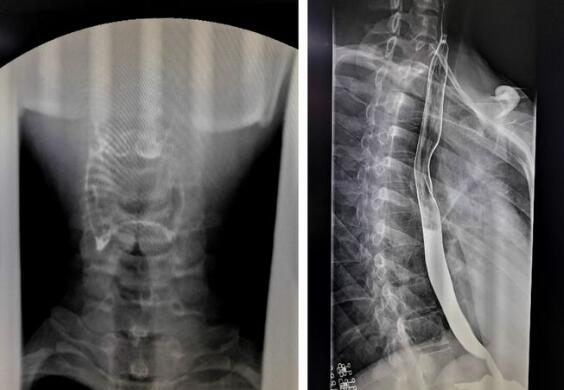

数字化胃肠机拍摄的上消化道造影图

1、上消化道造影,能显示咽部到十二指肠的影像。